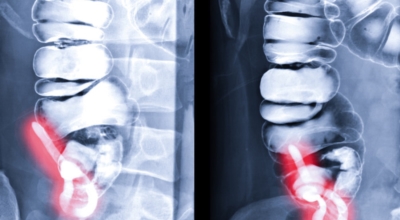

맹장염 치료방법

대개 치료의 경우 수술을 진행하는 것이 가장 대표적이며 충수 돌기의 절제를 진행합니다. 항생제를 투여하고 이후 수술을 진행하는데 수술 후에는 금식이 필요합니다. 예외적으로 염증이 심각하여 고름이 발생하면 해당 고름을 우선 제거하고 이후 항생제를 통해 염증을 가라앉힌 후 수술을 진행합니다.

맹장염 초기 증상을 인지하고 병원을 방문하여 맹장염이라고 진단을 받게 되면 복강경 수술로 30분 이내 비교적 안전하게 수술을 마치게 되어요. 하지만 급성 충수염으로 맹장이 터져서 복막염이 생기게 되면 수술도 까다롭고 시간도 훨씬 길어지게 돼요. 급성 충수염의 경우 드물게는 염증이 심해 박리가 안되어 소장과 대장 일부를 절제해야 하는 경우가 생기고 수술 범위가 커져 복강경 수술에서 개복수술로 전환하는 경우가 일어날 수도 있으며 개복수술을 시행할 경우 상처가 커질 수 있어요.